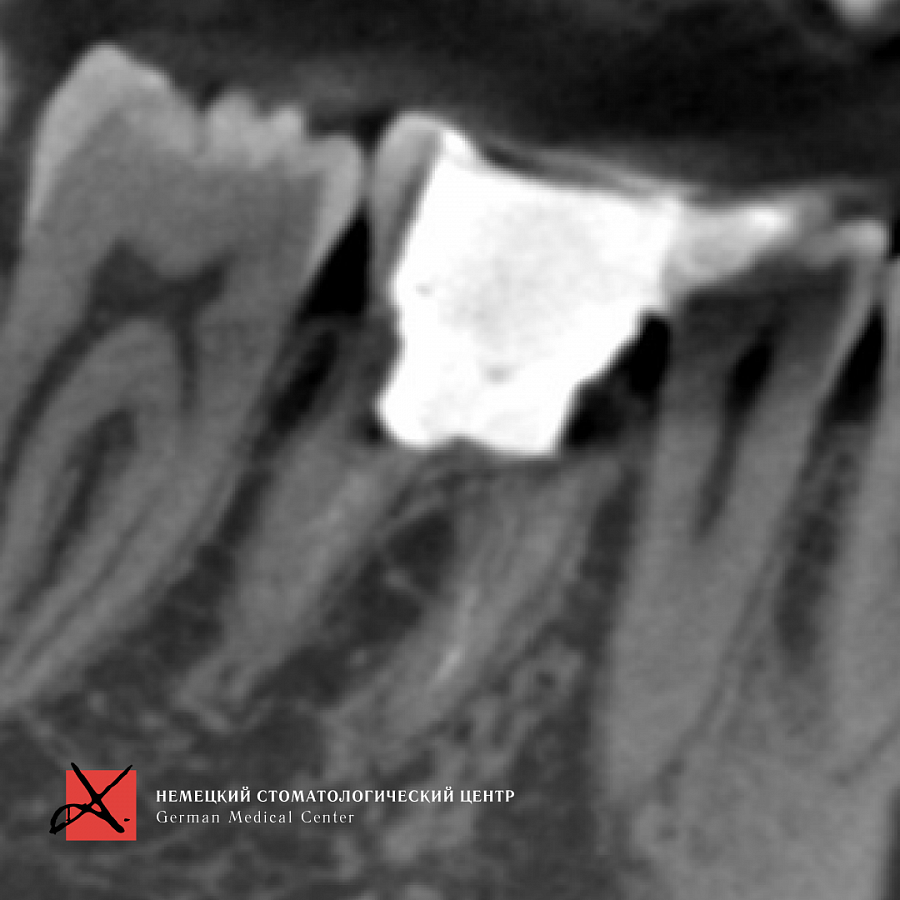

Пациент направлен врачом-терапевтом для удаления зуба 46 (нижний шестой зуб справа) и одновременной постановки имплантата.

Зуб был фрагментирован, чтобы удаление прошло максимально атравматично, то есть без повреждения окружающих костных стенок. После удаления установлен имплантат. Операция прошла успешно, пациенту уже установлена зубная коронка.